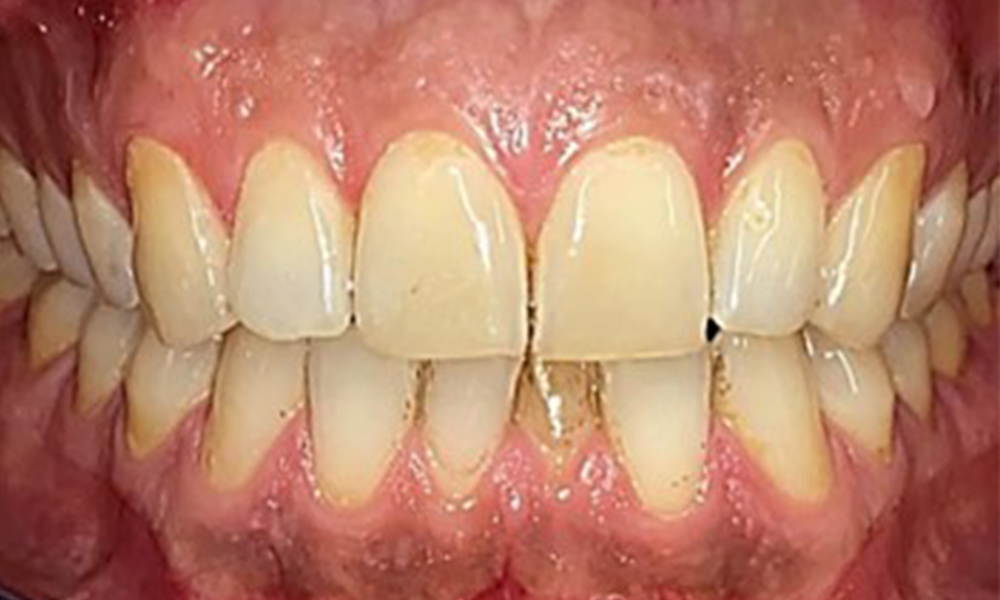

Frontal view

Fig. 2 Frontal view, © Dr R. Krapf

There were no pathological extraoral findings. During intraoral examination, inspection of the frontal view revealed brownish discolouration near the keratinised gingiva and at the transition to the moveable mucosa (Fig. 2), which could be attributed to nicotine consumption. Whitish mucosal lesions were observed on the palate, particularly near the maxillary molar palatal surfaces, indicating increased keratinisation and can also be attributed to nicotine consumption. The tongue was covered with a removable white and brownish coating.

The patient has full dentition with a total of 28 teeth. There were noteworthy erosions and attritions. (Fig. 4, Fig. 5). Due to bruxism, the patient has been wearing a splint with an adjusted bite block at night for many years. The erosions were caused by long-term consumption of isotonic beverages. No periodontal bone loss or active caries were observed.